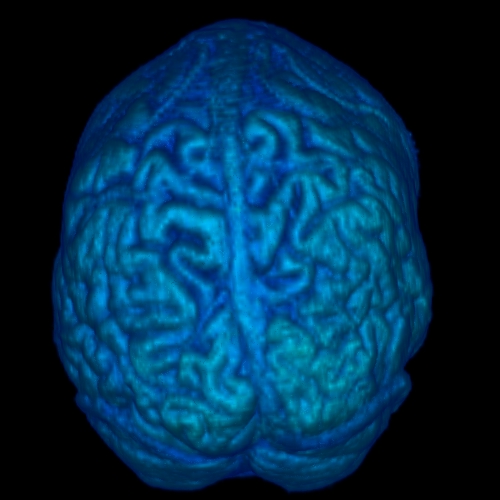

Three dimensional reconstructions of the scalp and neural tissue were created using the software AVS by stacking, transforming and rendering the MR data using ray tracing. Here are images of the reconstructed scalp and neural tissue.

Scalp Reconstruction Brain Reconstruction Brain Reconstruction Brain Reconstruction

Scalp Posterior View of Neural Tissue Anterior View of Neural Tissue Lateral Right View of Neural Tissue

Computer animations of the scalp and brain rotating were made using the software AVS. These were created using isosurfaces, rather than ray-tracings. Here is a movie of the scalp rotating (QuickTime format, 11.0Mb or AVI format, 0.7Mb) and a movie of the brain rotating (QuickTime format, 6.6Mb).